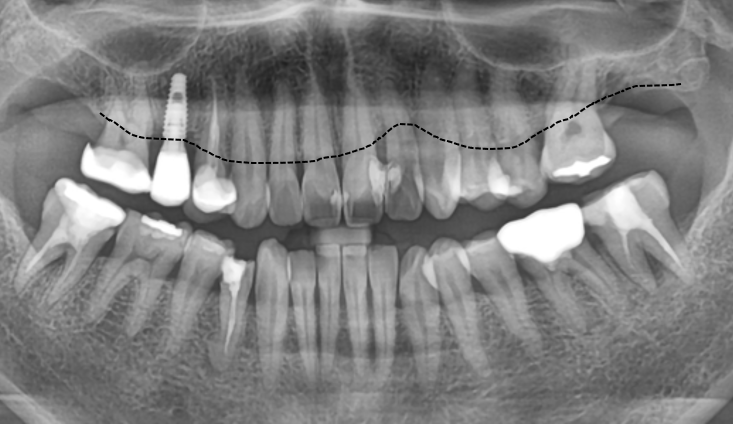

엑스레이에서 현재 환자분 뼈 상태를 그려봤는데요.

앞니 쪽에서 뼈 흡수가 많이 되어 라인이 위로 올라가는 것을 볼 수 있었고, 만져봤을 때 경미한 흔들림도 있었죠..

환자분께 현재 상태의 심각성을 말씀드렸어요.

"지금은 색이랑 형태보다 잇몸 뼈가 흡수되는 게 더 문제입니다. 레진이 분리가 되어서 사이가 닦여야 하는데 붙어있어 관리가 되지 않는 형태예요."라고요.